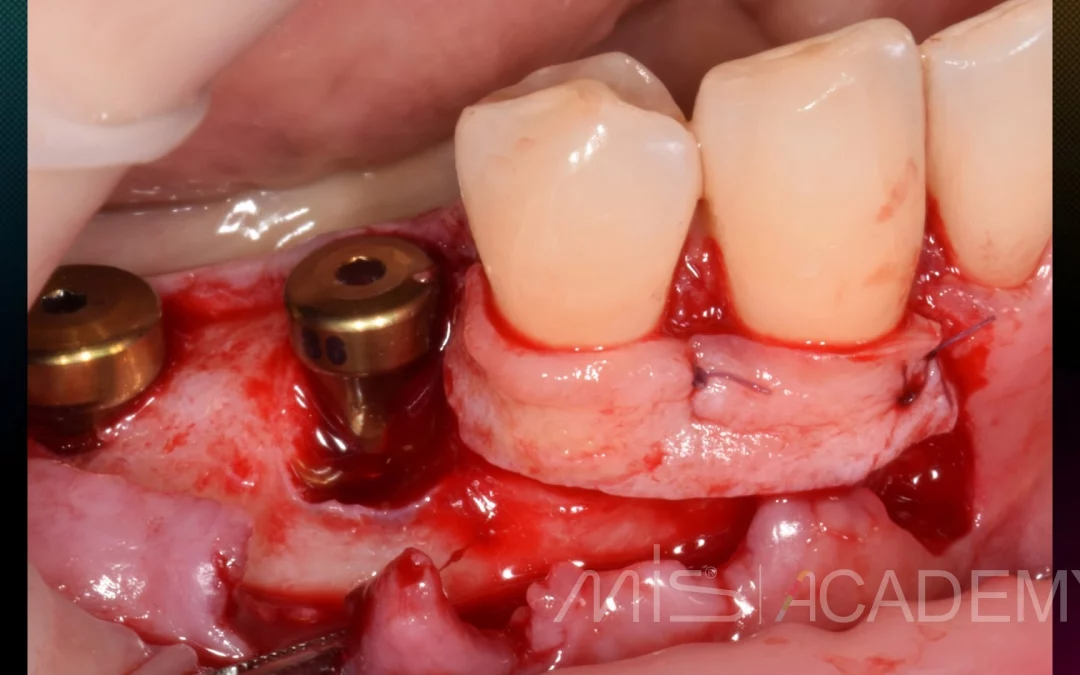

Юрий Гузеев | Клинический кейс YG-131

Восстановление объема и прикрепления. Работа с мягкими тканями в два этапа: 1 - Фиксация трансплантата к вестибулярному лоскуту. 2 - АСЛ. - Имплантаты MIS C1. - Connect. - Multi...